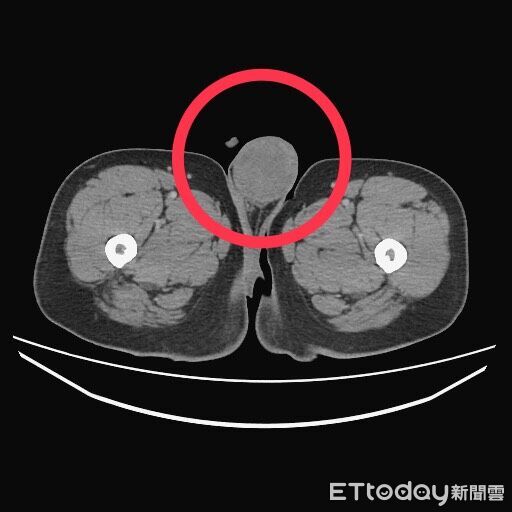

台中一名於七期百貨公司任職的30多歲男子,因連續發燒一個月且咳嗽不止,起初以為只是普通感冒或流感,多次前往診所就診服藥。由於該名男子身材壯碩,自恃年輕體健,認為「忍一下就好」,未曾警覺病情異樣。直到症狀加劇,出現咳血、甚至坐著也喘不過氣的嚴重情況,才緊急前往大醫院掛急診,一查確診是睪丸癌末期,身體幾乎被腫瘤塞爆,入院後連病理報告都還沒出來,就已經器官衰竭死亡。

ETtoday